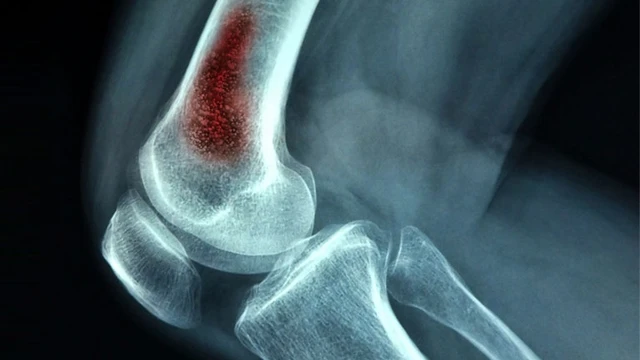

Ung thư mô liên kết là một loại ung thư hiếm, xuất phát từ xương hoặc các mô liên kết như cơ bắp, mô mỡ, thần kinh, mạch máu và các mô lân cận xương và khớp. Triệu chứng của bệnh này phụ thuộc vào kích thước và vị trí của khối u. Các phương pháp điều trị có thể bao gồm phẫu thuật, hoá trị, xạ trị, liệu pháp miễn dịch hay liệu pháp nhắm trúng đích.